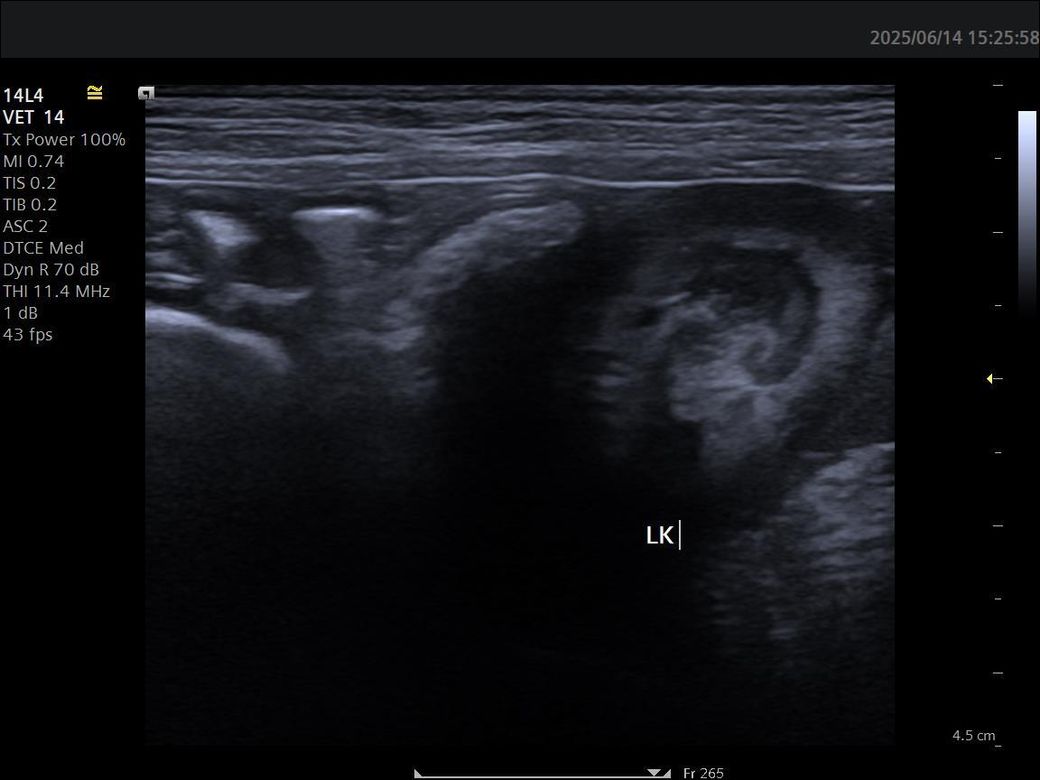

강아지 신장 사진입니다.이상한부분있을까요

4살 8개월 비숑인데 신장혈액상으로 정상인데 사진으로 어떤분이 궁상동맥 석회양상이보인다고하는데 궁상동맥 석회양상이라는게 석회화로진행되지는 않고 그전단계라는건가요?그거 없앨려면어떻게해야하나요

없어지지 않습니다. 일반적으로 정상적인 노령성 변화로 궁상동맥 벽에 칼슘과 같은 무기질이 침착된 양상을 의미합니다. 큰 의미를 두지 않는 변화입니다.